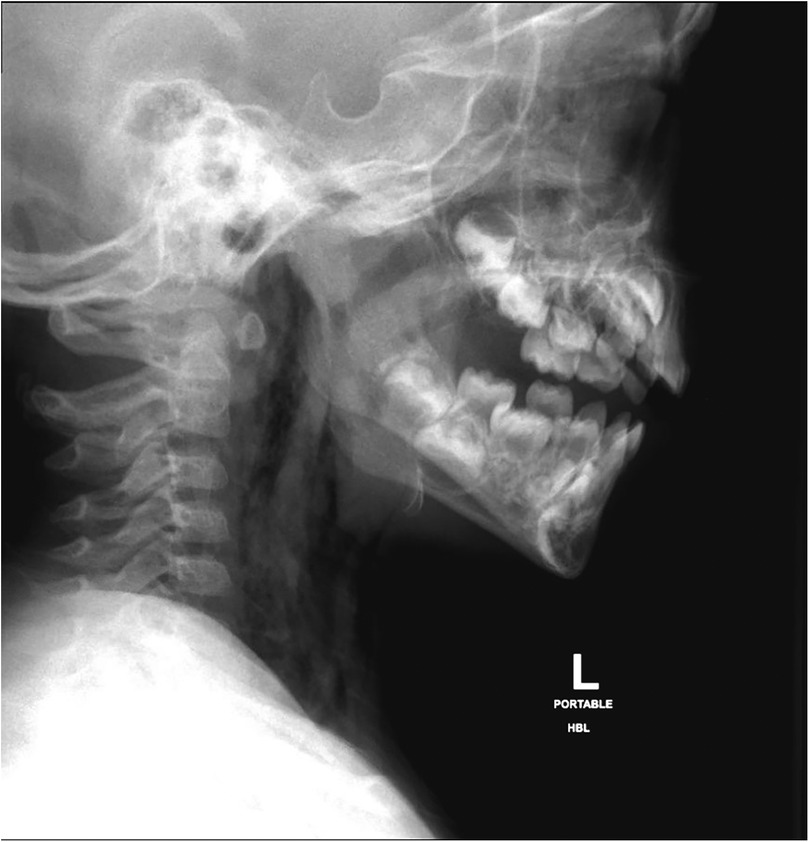

Oropharyngeal injuries in young children, though common, carry the potential risk of serious complications. Here, we describe a rare case of a toddler with a minor penetrating injury in the hypopharynx leading to perforation, surgical emphysema and pneumomediastinum. A 2-year-old boy was brought to the emergency department with noisy breathing and shortness of breath started after a traumatic injury with a pencil in the mouth. He was found to have tachycardia, tachypnea, grunting but no stridor or retractions. A brief oral exam showed a blackish discoloration in the posterior pharyngeal wall, and crepitations were palpated on the neck. Imaging revealed extensive subcutaneous emphysema and a defect in the posterior oropharyngeal wall. He underwent surgical repair of the pharyngeal defect and was later discharged in stable condition. This case highlights the need for vigilance in assessing oral impalement injuries in children, as such injuries can lead to significant complications. Early detection and management is crucial to prevent severe outcomes. The case underscores the importance of careful clinical and radiological evaluation in managing pediatric oral impalement injuries.